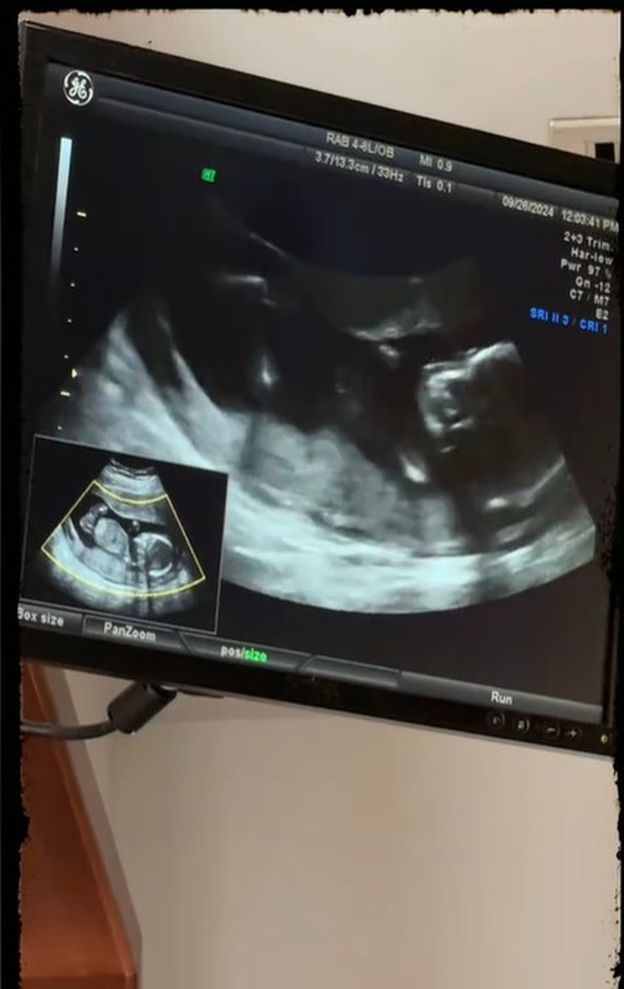

Artistul îi arăta fiului său o ecografie în care se vedea bebelușul încă nenăscut și îi spunea că acolo se află frățiorul său.

„Asta-i burta lui mami, aici. Și aici e frățiorul”, i-a spus Culiță fiului său, în clipul publicat de Daniela Iliescu pe internet.